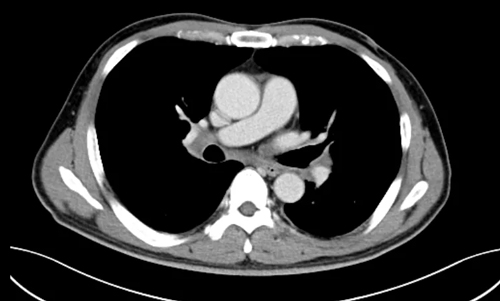

兩周期化療結(jié)束后

復查CT

腹盆腔內(nèi)、腹膜后及雙側(cè)腹股溝結(jié)節(jié)

對比之前

已明顯縮小、部分消失

原脾臟內(nèi)多發(fā)結(jié)節(jié)狀低強化影

已未見顯示

胸悶、氣喘、盜汗的癥狀也逐漸消失

( 化療后)